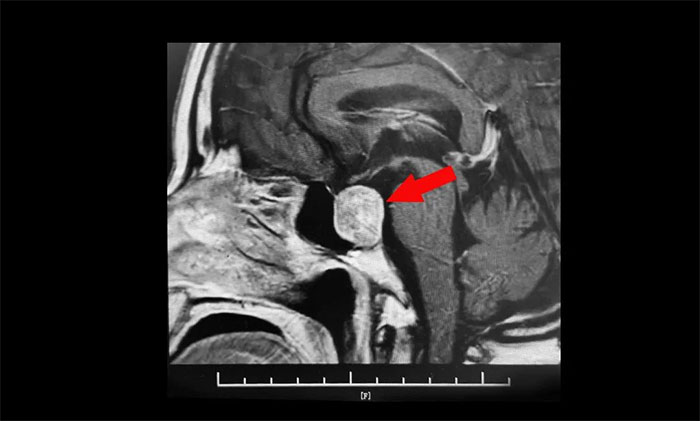

鞍区MRI平扫+增强显示:蝶鞍显著扩大,鞍区见肿块信号,大小约29*19*24mm;垂体柄明显缩短左偏;病变向鞍上生长,占据鞍上池,推移视交叉;向鞍旁生长,侵及右侧海绵窦,右侧海绵窦内颈内动脉被推压、包绕,右侧颈内动脉海绵窦段较对侧稍细。

▲ 肿瘤侵袭生长,包绕颈内动脉,knosp分级Ⅲ级

针对该患者,治疗方式就是手术切除肿瘤,减除肿瘤压迫。目前手术方式,主要有开颅手术切除肿瘤和经单鼻孔-蝶窦入路切除肿瘤。而该患者肿瘤如鸽子蛋大小,属于垂体大腺瘤,并且侵袭生长,侵及右侧海绵窦,右侧海绵窦内颈内动脉被推压、包绕,knosp分级Ⅲ级,向上已突破鞍隔压迫视神经、视交叉、下丘脑;向下侵蚀充满蝶窦。